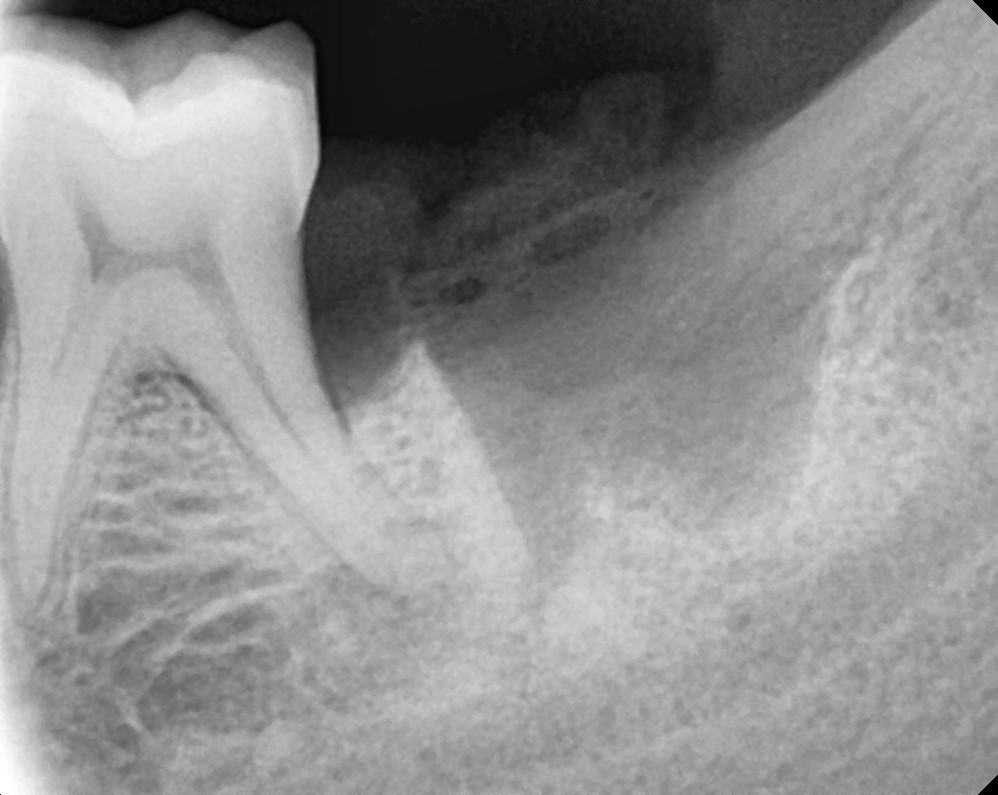

Lower 3rd Molar

After After

Before Before